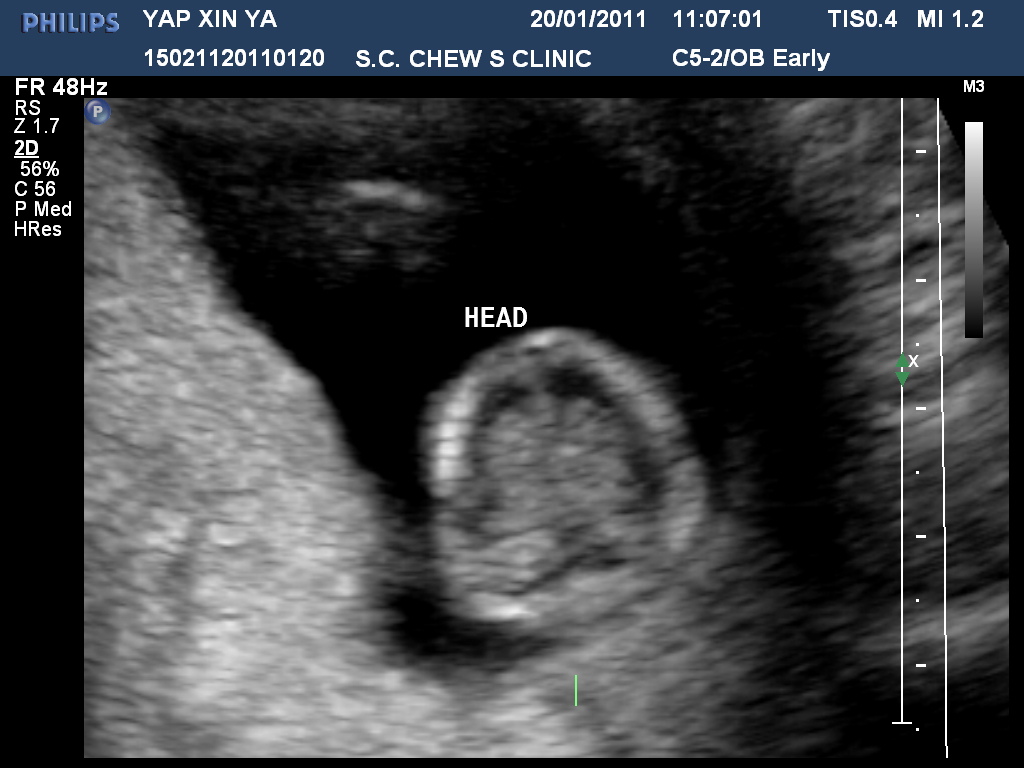

Went back to the clinic...still amazed by the baby pictures...LOL...Was looking forward to see my baby's progress. So, the basic measure my weight and blood pressure. My baby was looking BIG! I think it was 7cm if i am not wrong. i was officially 3 months pregnant that day. which was 12 weeks pregnant. So, the legs were formed, I could see the fingers and and toes..and heartbeat. aww....I had a miniature human being inside me. lolz...Here's the pictures: